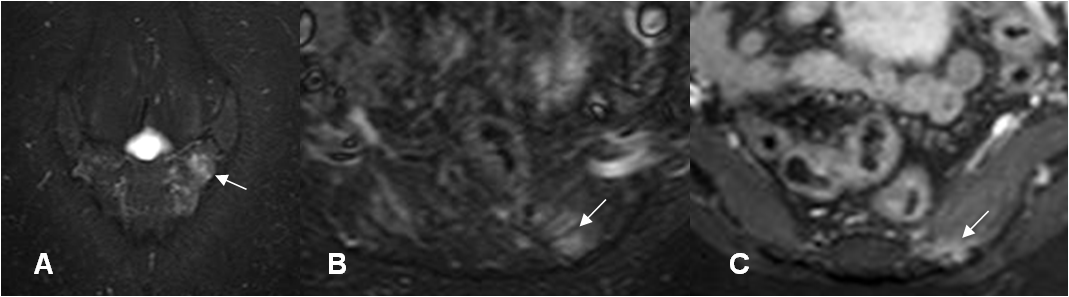

Fig 58 F. Entesitis.

A: RM coronal en STIR. Aumento en la señal sobre el alerón izquierdo del sacro, por osteitis.

B: RM axial en STIR y C: RM axial en T1 STIR, con contraste. Aumento en la señal en la inserción del músculo piramidal, con realce del contraste, por entesitis.